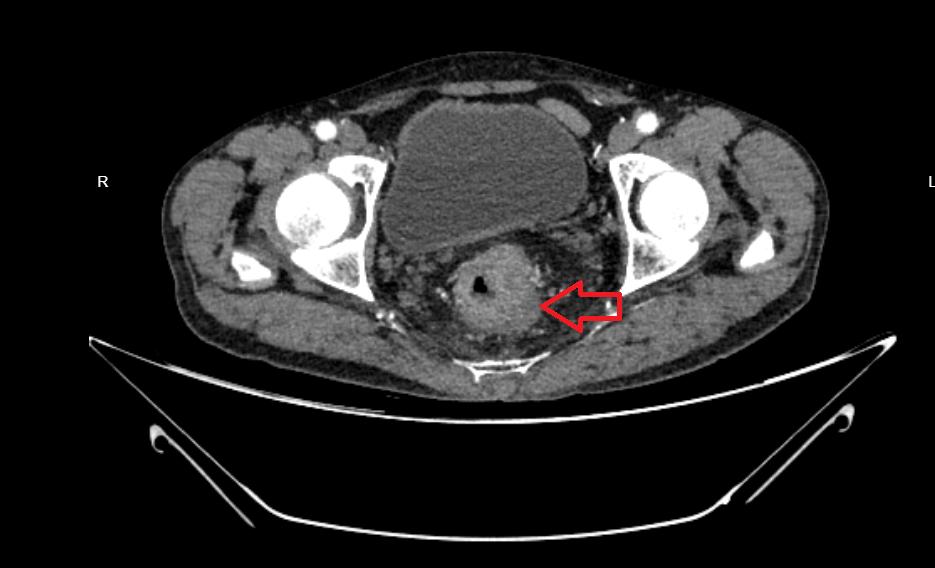

4月10日57岁的张叔叔因“大便习惯改变8月”到外一病区苟定奇医生处就医。CT提示直-乙交界段结肠壁不均匀增厚,增强后呈明显强化,考虑恶性肿瘤性病变,累及外壁、左侧肛提肌;肠镜下活检:(直肠粘膜)活检组织:腺癌。诊断:直肠恶性肿瘤(T4Bn1m0 ⅢC)伴梗阻。

为保证二期手术的成功,保障造口近端有足够长的肠段用于与直肠下段吻合,外一病区医疗团队术前细致评估影像资料,判断肿瘤范围,为患者行一期手术时选取了合适位置行乙状结肠双腔造口术,术毕转入肿瘤科进一步行放疗+卡培他滨化疗。

于7月8日患者按计划再次来院,经3月放化疗后增强CT及增强MRI均提示直肠上段肿物较4月明显减小,周围间隙清楚,适宜开展二期手术,7月14日手术过程中外一病区医疗团队竭力发挥腹腔镜手术优势,精准切除直肠肿瘤的同时予造口还纳,为患者避免了开腹扩大伤口或二次造口需三期手术的风险,整台手术耗时不到3小时,术中出血仅15-20ml,成功按计划完成了对患者的治疗。